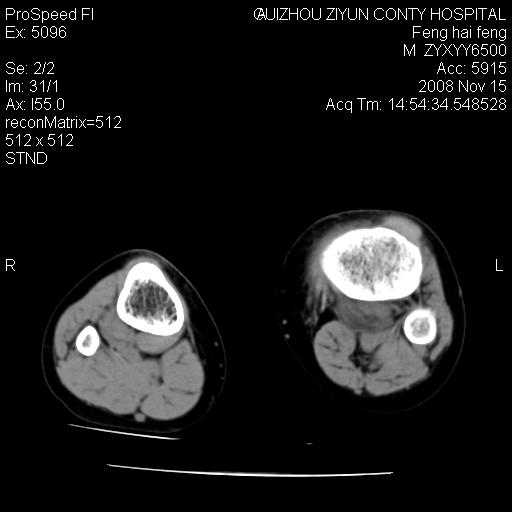

标题: CT16656:M 14Y 左膝关节肿胀一年余。其余病史不详。 [打印本页]

标题: CT16656:M 14Y 左膝关节肿胀一年余。其余病史不详。

考虑左侧髌骨结核;左膝关节滑膜肿胀、增厚,关节囊积液。

左膝滑膜型关节结核可能性大!支持!滑膜型关节结核主要ct表现:关节囊肿胀,积液,关节面见小破坏灶,并见点状死骨!

好大的左腿!考虑左侧髌骨结核,左膝关节滑膜肿胀、增厚,关节囊积液。

左侧髌骨结核;左膝关节滑膜肿胀、增厚,关节囊积液